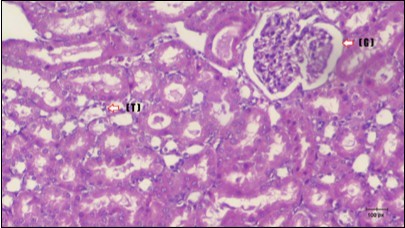

Kidney Histopathological Observations

Kidney sections of diabetic rats showed an increase in mesangial cell and matrix of glomeruli with increase in glycogen deposition and hyalinization of arterioles with thickened basement membranes of proximal and distal convoluted tubules. These changes will lead to progressive reduction in the filtration surface of the glomeruli 35. Histological examination of the kidney of the control rats showed normal structure of renal glomerular. The proximal and distal tubules were lined with normal epithelium (Figure 13). The diabetic rats showed tubular casts, inflammatory cellular infiltration and glomerular atrophy (Figure 14). Kidney of rats in groups (3 and 4) showed some glomeruli return to be normal (G). Focal tubules casts (T) in Fenugreek group and some normal tubules in the Glimepiride group with no inflammatory cellular infiltrate in both groups (Figure 15 and Figure 16). However, kidney of rats in group (5) showed normal glomerular (G), normal tubules (T) with no tubular casts (Figure 17).

Figure 17.Photomicrogragh of kidney section of treated rat with both Fenugreek and Glimepiride showing improved cortical tissue with most of both Bowman,s capsules (arrow) and proximal tubules (dash-arrow) with nearly normal structure .Note distal tubules still suffering (star). (H&E) (40X).

Photomicrogragh of kidney section of treated rat with both Fenugreek and Glimepiride showing improved cortical tissue with most of both Bowman,s capsules  (arrow) and proximal tubules (dash-arrow) with nearly normal structure .Note distal tubules still suffering (star). (H&E) (40X).